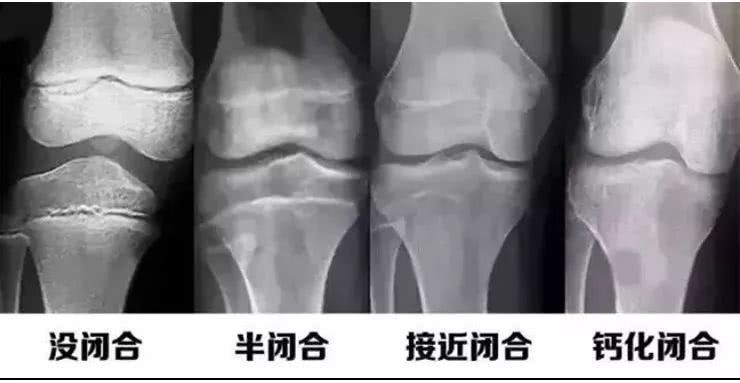

小张两口子,一个1.85米,一个1.68米,可是小小张今年13岁了,但看起来比同龄的孩子却差一大截,甚至有比小小张年龄小很多的孩子都比小小张高出很多。按道理不应该呀,父母都是挺高的,小小张怎么会不长高呢?是什么原因呢?最后小张夫妇下定决心,决定还是带孩子去医院看看,到底是不是晚发育。结果发现小小张骨骺愈合只剩一条缝了,根据其闭合程度来预测小小张长高空间已经不大了,原来是小小张青春期开始较早,最终身高矮小。

到底是什么原因导致小小张早熟呢?原来小张夫妇平时比较忙,小小张要买吃的,就总是给钱让小小张自己去买,孩子怎么能抵挡花花绿绿的包装,麻辣鲜香的垃圾食品的诱惑?钱就全买垃圾食品了,总是垃圾食品,那就很容易影响到孩子的身高发育。幸运的是小小张骨骺线还没有完全闭合,还有希望,最后医生根据小小张闭合程度来预测长高空间,制定科学的身高管理方案,有计划的增高身体,这个结果就不用多说了。